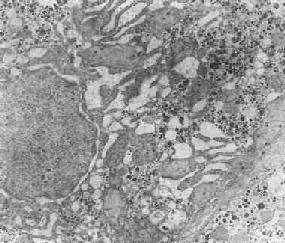

在由各种原因引起的细胞变性和坏死过程中,粗面内质网的池一般出现扩张,较轻的和局限性的扩张只有在电镜下才能窥见,重度扩张时则在光学显微镜下可表现为空泡形成,电镜下有时可见其中含有中等电子密度的絮状物。在较强的扩张时,粗面内质网同时互相离散,膜上的颗粒呈不同程度的脱失。进而内质网本身可断裂成大小不等的片段和大小泡(图1-6)。这些改变大多见于细胞水肿时,故病变不仅见于内质网,也同时累及Golgi器、线粒体和胞浆基质,有时甚至还累及溶解体。

图1-6肝细胞粗面内质网扩张